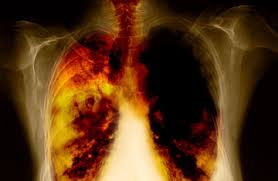

Lung cancer is a growth of malignant cells in the lungs.You see, throughout your life the cells in your body continually divide and reproduce. Now, for the most part, this all takes place in an orderly manner as your cells go about doing their job of meeting the needs of your body. Lung cancer is the growth of these malignant cells in the lungs.Most often, the malignant cells are believed to form in the epithelial lining of the airways, where the oxygen is extracted from the air we breathe. This is why lung cancer is sometimes referred to as bronchogenic carcinoma (cancer arising from the bronchia). A relatively small percentage of lung cancer (10% or less) begins in the pleura, the thin tissue sac that surrounds the lungs. These cancers are called mesothelioma. The rarest form of begins in the blood vessels or other supporting tissues of the lungs.

Cancer of the lungs is one of the deadliest forms of cancer. This is primarily due to the fact that lung cancer tends to metastasize early in the process of the disease and is often not discovered until it's spread. Additionally, when it does metastasize, it tends to spread to the most vital yet vulnerable organs of the body. Finally, because the lungs are so susceptible to metastatic cancers from other sources throughout the body, it's not uncommon to find a cancer in the lungs that is not lung cancer but a metastatic cancer. These cancers tend to make their home in the peripheral tissues of the lungs rather than the primary tissues.